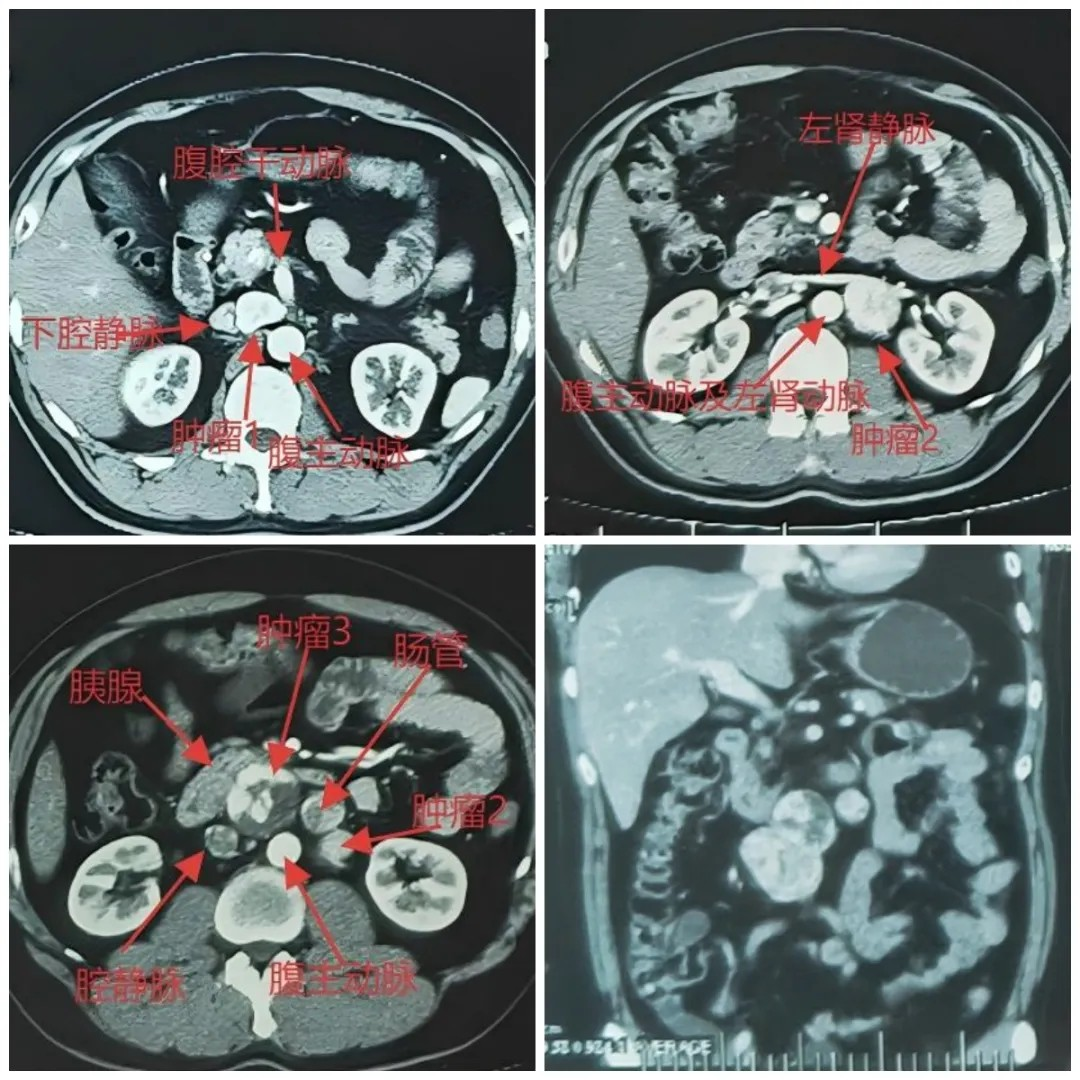

近日,河北医科大学第二医院泌尿外科王东彬团队在多学科协作下,成功为一名被多发嗜铬细胞瘤困扰两年的患者实施手术。经过近 8 小时的精密操作和术后 120 小时的悉心守护,患者闯过 “鬼门关”,血压恢复稳定,顺利转...